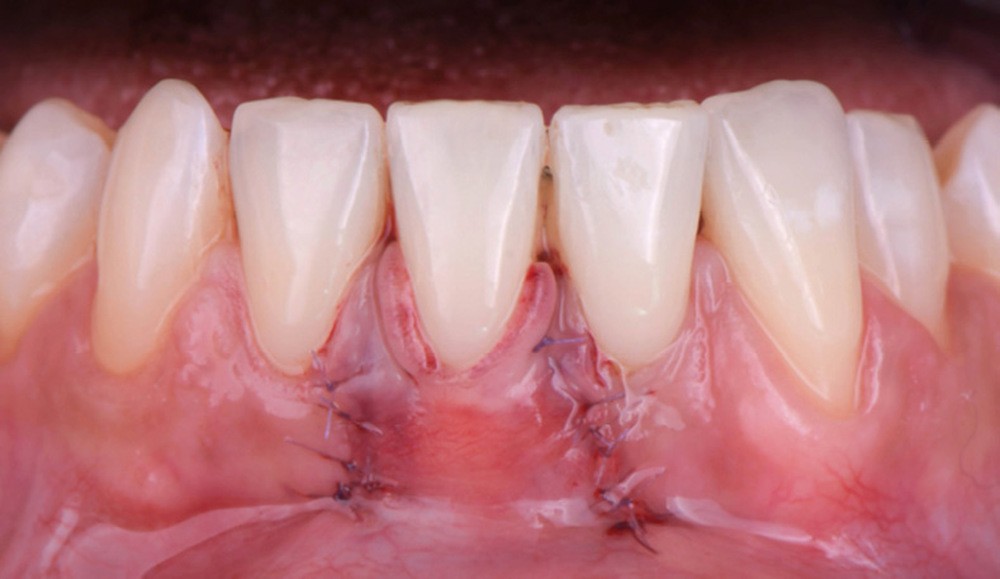

Selon le Dr Sylvie Pereira, lors de la réalisation de cette technique, le lambeau d’épaisseur partielle est suturé apicalement par trois points de sutures périostées matelassiers horizontaux. De plus, elle préconise de positionner le nœud du point de suture si le greffon est fin pour le maintenir au plus près du lit receveur.

La stabilité du lambeau est primordiale dans la réussite de cette technique de recouvrement. En cas d’instabilité, même en l’absence d’erreurs techniques, l’analyse de certains facteurs liés au patient est indispensable. Afin de maintenir la stabilité du lambeau jusqu’à la dépose des points, le praticien doit veiller à l’adéquation du contrôle de plaque effectué par le patient, à l’absence de mastication impliquant la zone d’intervention, à la prévention de tout traumatisme ou de modifications des conditions locales par le patient.

Selon le Dr Sylvie Pereira, contrairement au maxillaire où la hauteur du lambeau déplacé coronairement est déterminée par la profondeur de la récession, à la mandibule, les incisions horizontales sont placées de manière à obtenir au moins 2 mm de tissu…